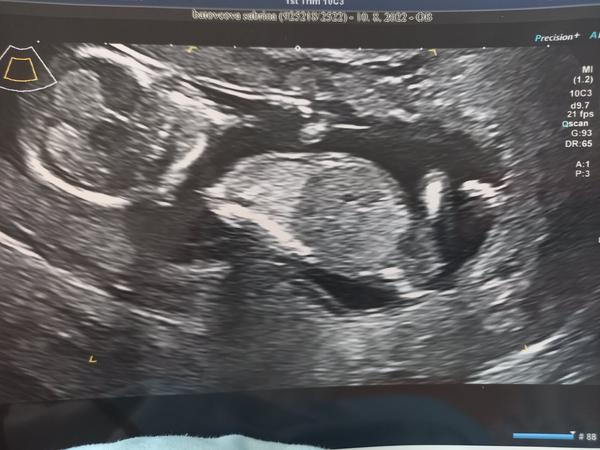

Vidíte pohlavní hrbolek na 1. screeningu?

Ahoj, dne 10.8. jsem byla na 1.screeningu, byla jsem ten den 13+1. Pohlaví si asi neplánuji říct,ale i tak dumám pořád nad těmito fotkami a snažím se najít třeba pohlavní hrbolek. Pro zkušenější, nevidíte tam hrbolek,popř. co byste hádali?🙊